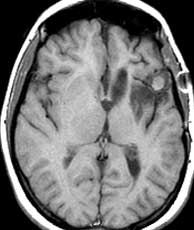

T1 pre-gad T2 MRA

Diagnosis: Aneurysm of the left cavernous internal carotid artery.

Cavernous sinus ICA aneurysms are more common in women and typically present over the age of 50. They may cause palsies of cranial nerves 3, 4, 6, as well as the first and second divisions of the trigeminal nerve since these nerves lie within the cavernous sinus. A variable amount of thrombosis may be present. In this case, the aneurysm is most likely partially thrombosed due to the complex, layered signal. The presence of the phase encoding artifact proves that there is at least some flow. Related Cases